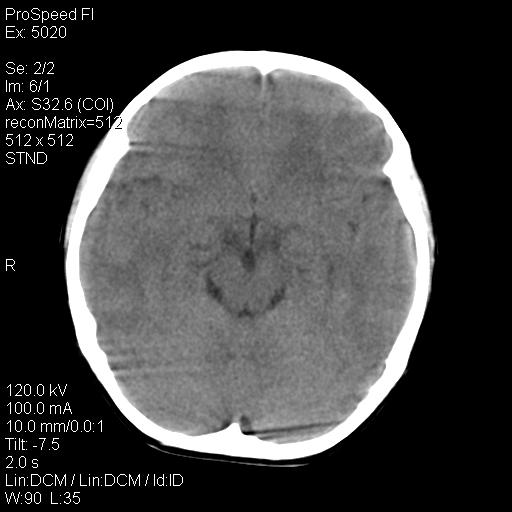

标题: PED1637:M 6Y 顶部无痛性包块两月。 [打印本页]

标题: PED1637:M 6Y 顶部无痛性包块两月。

2、颅骨局部缺失,边缘光滑、整齐

颅骨为好发部位,生长缓慢,常位于顶骨、枕骨及颞骨,表现为颅骨缺损,呈圆形或椭圆形,边界清,无硬化

事发冠状缝与矢状缝交界区,密度较低,考虑表皮样囊肿可能性大,其次不除外嗜酸性肉芽肿